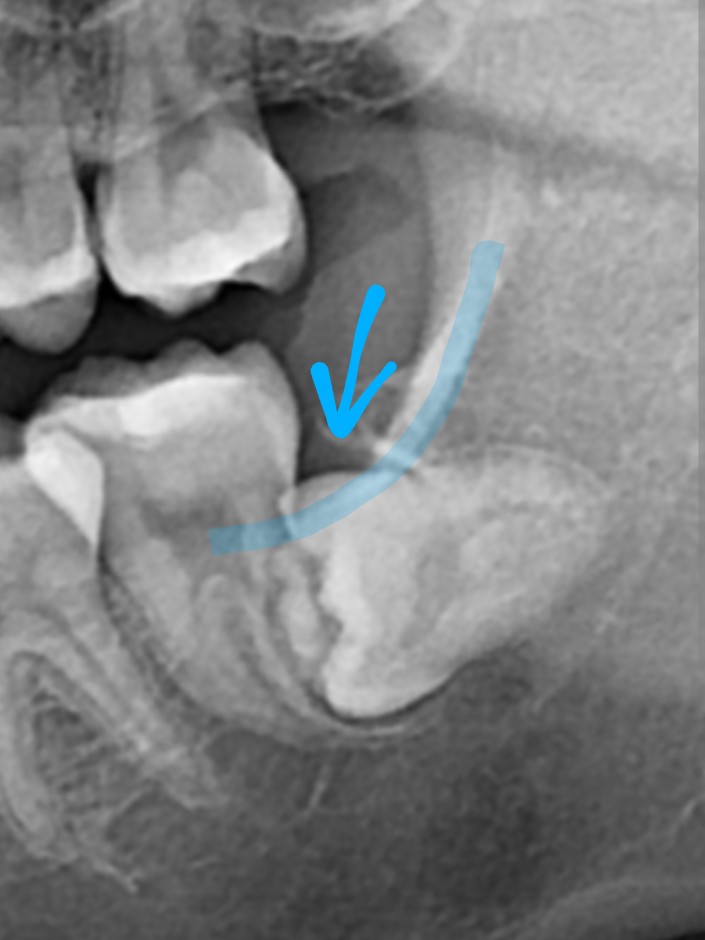

wendy113089 : 單看下排就很亂QQ101.10.9.126 10/06 15:46

wendy113089 : https://i.imgur.com/rvVnMjr.jpg101.10.9.126 10/06 15:46

leoth : 好歪喔49.217.131.93 10/06 15:53

Sanish : 推文圖這很歪吧,感覺會有清潔死角114.39.214.42 10/06 16:10

Sanish : ,真的要矯正114.39.214.42 10/06 16:10

Nemophila : 這個要矯正 感覺都擠在一起了 59.126.91.141 10/06 16:41

k8530908 : 下排真的明顯亂 覺得整齊的是比原p223.141.217.129 10/06 20:21

k8530908 : o更慘嗎223.141.217.129 10/06 20:21

skyyo : 也有冒小角的水平智齒 下圖是網路牙 39.12.73.25 10/07 15:34

skyyo : 醫診所的類似案例 39.12.73.25 10/07 15:34

skyyo : http://i.imgur.com/p1FKj38.jpg 39.12.73.25 10/07 15:34